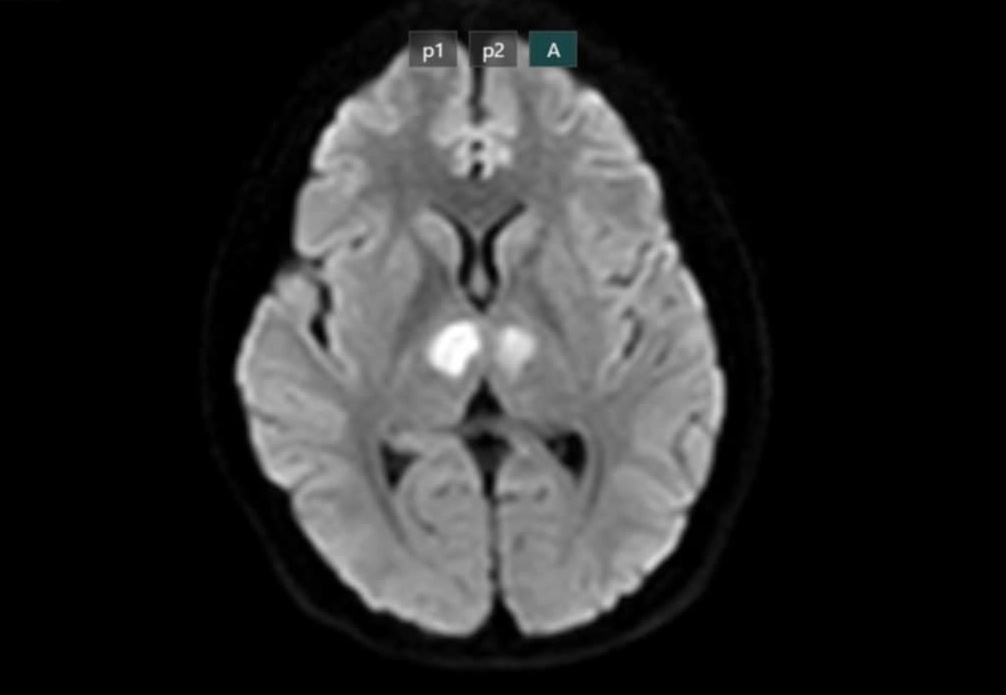

Kết quả chụp MRI cho thấy năo bệnh nhân có h́nh ảnh tổn thương vùng đồi thị hai bên. Gia đ́nh xin chuyển bệnh nhân sang Bệnh viện Bạch Mai để được tiếp tục điều trị. Kết quả xét nghiệm loại thuốc giảm cân bệnh nhân uống cho thấy dương tính với thành phần Sibutramin.

Năo bệnh nhân bị tổn thương nặng. Ảnh: BSCC